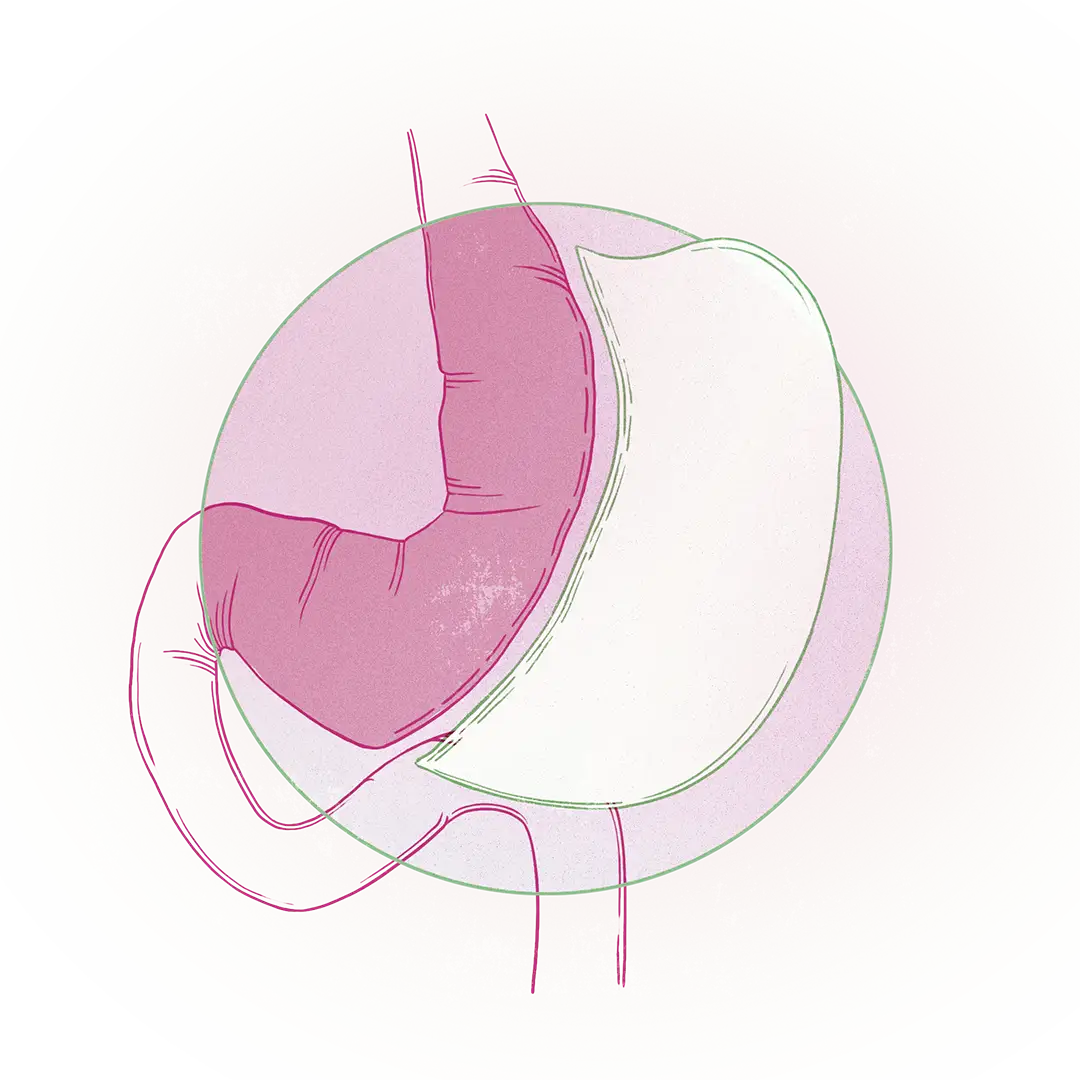

La cirugía bariátrica se realiza mediante laparoscopia —incisiones mínimas en cinco zonas del abdomen—, proceso que facilita en gran medida la recuperación. "Se realizan cinco incisiones pequeñas, la más grande de 12 mm. El paciente puede estar caminando el mismo día de la cirugía; sin embargo, se recomienda permanecer en el hospital entre 24 y 36 horas para minimizar cualquier riesgo. Después de 15 días, la persona debe reanudar su vida normal", agrega el doctor Ospina.

- Cirugía bariátrica restrictiva: Restringe los volúmenes de comida que el paciente puede ingerir al eliminar quirúrgicamente un 80% del estómago. En esa categoría hay una operación avalada que se conoce como manga gástrica.